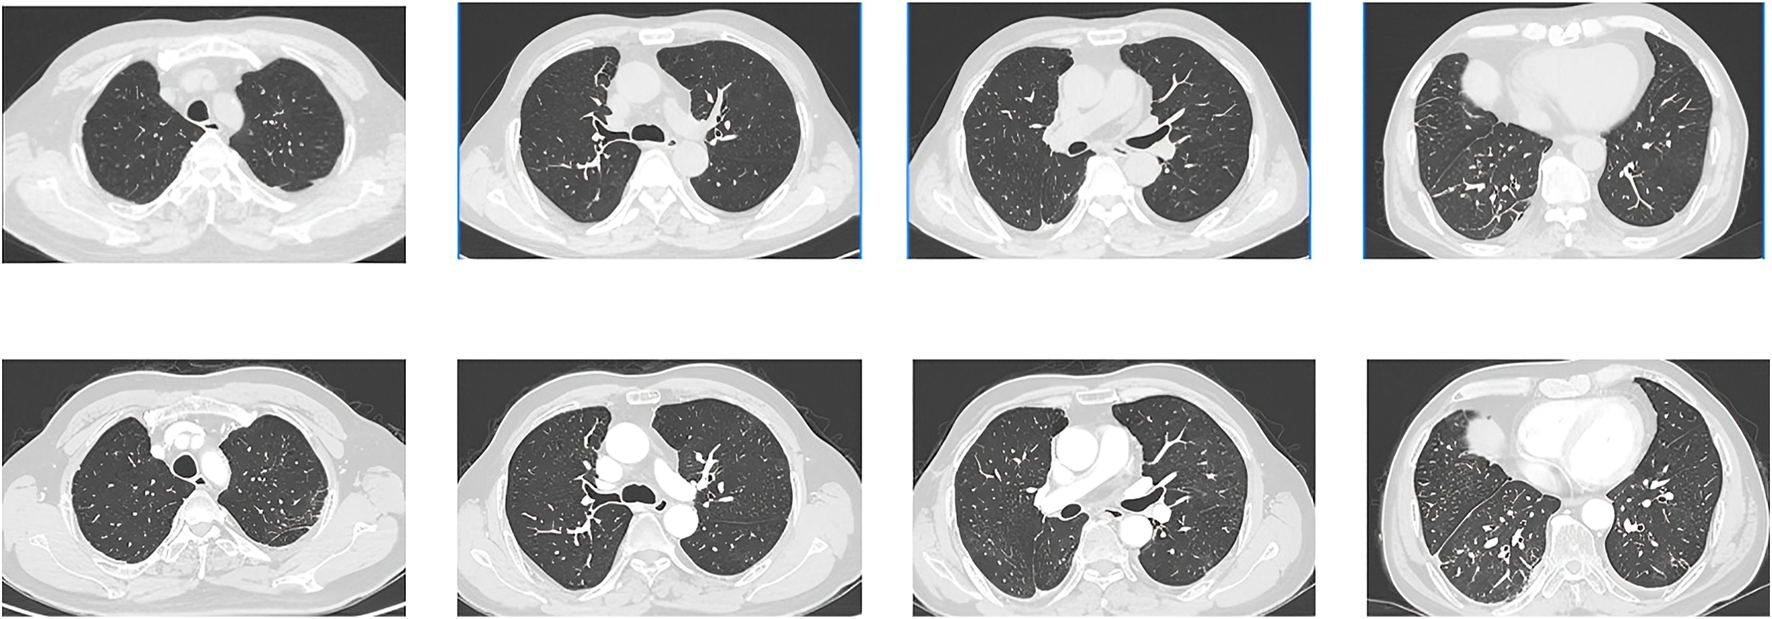

FIGURE 2

CT images obtained on 11 May 2022. The images showed the range of the lesions further extended with the interlobular septal thickening.

FIGURE 3

CT images obtained on 2 March 2022(UP) and 5 May 2022 (DOWN). The size of the metastatic lesion was reduced after pralsetinib treatment.

FIGURE 4

CT images obtained on 2 September 2022(UP) and 10 October 2023 (DOWN). The images showed that the ground-glass opacities, cystic lesions, and patchy consolidations had completely disappeared, and metastatic lesion size continued to be reduced.

It is noteworthy that the CT conducted on May 5th revealed a reduction in the size of the metastatic lesion (Figure 3), and the efficacy assessment indicated a partial response (PR) based on the Response Evaluation Criteria in Solid Tumors version 1.1 (RECIST 1.1). Due to the limited availability of alternative therapeutic approaches, patients have continued their antitumor therapy with pralsetinib. Subsequently, a follow-up visit was conducted after 3 months, during which the CT scan demonstrated the complete disappearance of ground-glass opacities, cystic lesions, and patchy consolidations, along with a further decrease in the size of the metastatic lesion (Figure 4). Over the ensuing 13 months, the patient faithfully adhered to the prescribed regimen of Pralatinib, and was regularly rechecked in the hospital, with no significant change in tumor size noted and no recurrence of any adverse events (Figure 4).